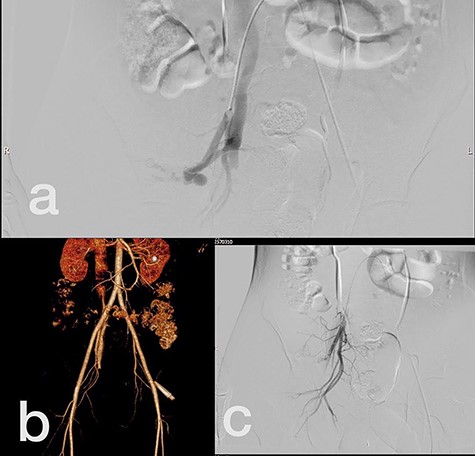

Sites of injury included 6 Posterior Tibialis arteries (27.2%) (Fig. 1), 2 deep femoral arteries (9.09%), 2 Superficial femoral arteries (9.09%) and 2 maxillary arteries (9.09%). We had only one injured artery (4.54%) in each of the following sites: internal pudendal a., Axillary a. (Fig. 2), Proneal a., Lumbar a., External carotid a., Anterior Tibialis a., common iliac a. (Fig. 3), temporal a., Thoracic aorta and Internal iliac artery (Fig. 4).

(a) Posterior Tibialis artery before intervention, (b) after endovascular stent graft deployment.

(a) Internal iliac artery before intervention, (b and c) after coil embolization.